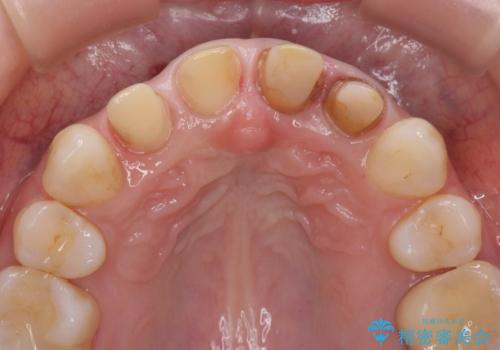

- 神経の死んでしまっている前歯の変色の改善を求めて来院されました。

根管治療をしたのち時間が経過して変色が目立つ歯と、レジン充填が複数箇所に及んでいる歯も同時にオールセラミック治療を行っていくこととなりました。

- 52.8万円(ジルコニアクラウン×4・仮歯×4)費用は治療当時の料金となります